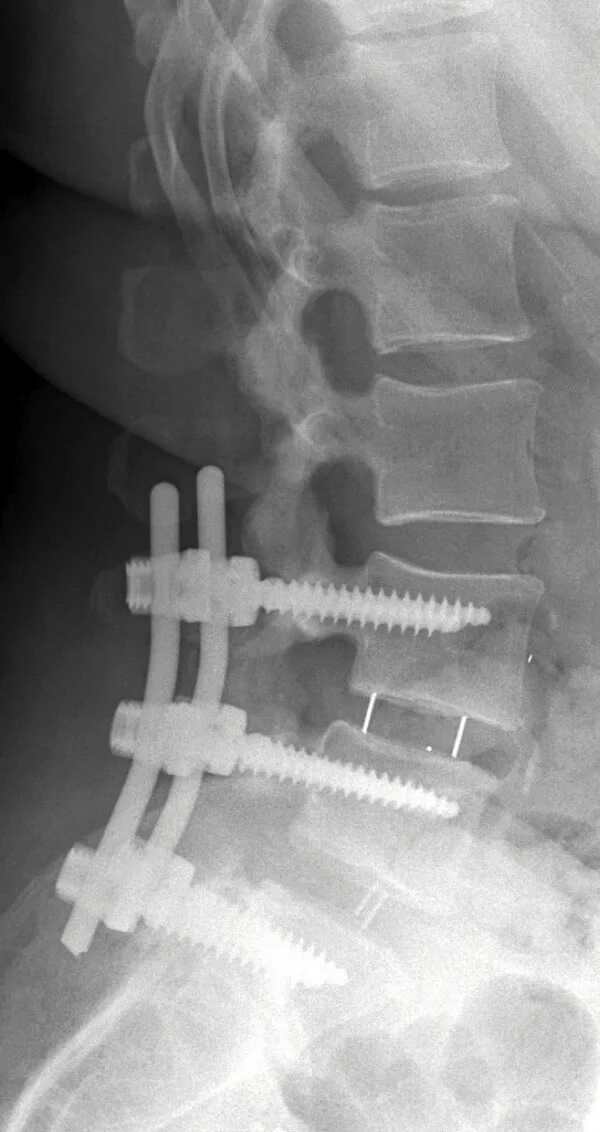

Установка кейджа в позвоночнике